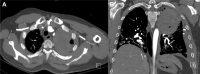

A 40-Year-Old Man With Tricuspid Atresia, Status Post-Fontan, With Severe COVID-19 Pneumonia and Pneumothorax

We report a case of COVID-19 in an adult single-ventricle patient post-Fontan-to our knowledge, the first report in this population documenting the use of the latest management recommendations for this novel disease. Additionally, this patient had significant pre-existing ventricular dysfunction, valvular disease, and comorbidities including HIV. (Level of Difficulty: Advanced.).